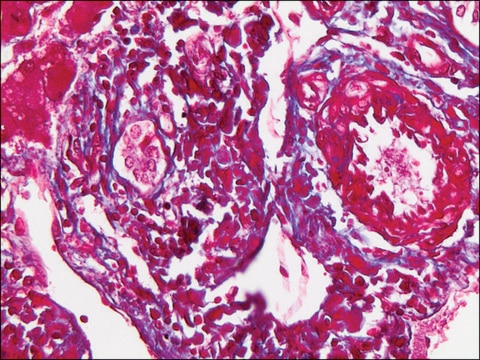

May be useful in study of diseases of connective tissue and muscle characterized by fibrotic and dystrophic changes.

Collagen and muscle fiber stain differentially when treated sequentially with Biebrich Scarlet-Acid Fuchsin, PTA/PMA and Aniline Blue. Cytoplasm and muscle fibers stain red whereas collagen displays blue coloration.

Clara Dees et al.

The Journal of experimental medicine, 208(5), 961-972 (2011-04-27)

Vascular damage and platelet activation are associated with tissue remodeling in diseases such as systemic sclerosis, but the molecular mechanisms underlying this association have not been identified. In this study, we show that serotonin (5-hydroxytryptamine [5-HT]) stored in platelets strongly